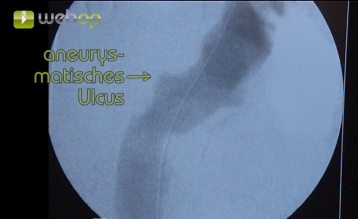

Im Beitrag wird die endoluminale Ausschaltung eines penetrierenden atheromatösen Ulkus (PAU, exzentrisch 32 x 24 mm) der Aorta descendens demonstriert. Wegen zweifacher gefäßchirurgischer Voroperation in der linken Leiste und schwerer Arteriosklerose erfolgt eine extraperitoneale Freilegung der A. iliaca externa.

Bei einem Durchmesser oder einer Tiefe des Ulkus von ≥ 20 mm ist eine elektive endovaskuläre Versorgung indiziert. Bei Hinweisen auf eine drohende Ruptur (Schmerzen, extraaortales Blut) ist die endovaskuläre Versorgung dringlich. Schmerz wird als eines der Hauptkriterien für ein dringliches operatives Vorgehen genannt.